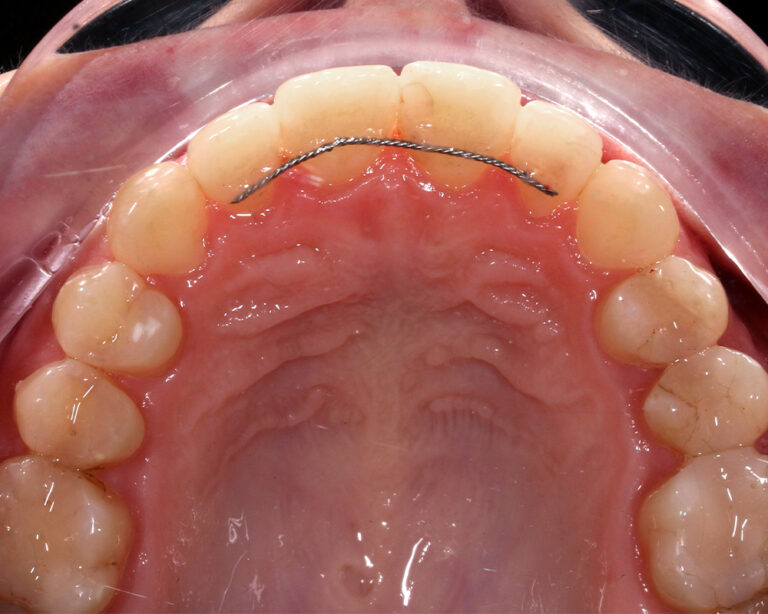

Кейс 13

Булгач (Мочалова) Галина Игоревна

Количество кап ВЧ 19

Количество кап НЧ 24

ДО

ПОСЛЕ